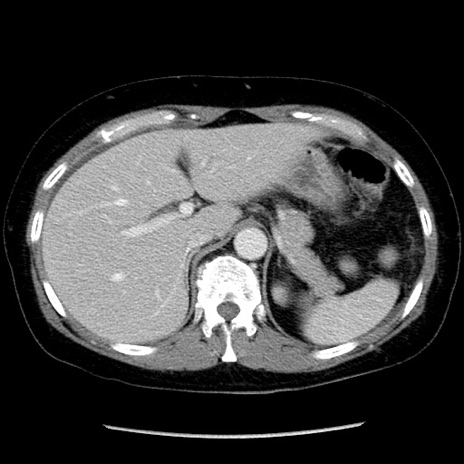

症例6(横断像)

【症例】50歳代女性

【主訴】下腹部痛

【現病歴】本日朝より下痢2回あり。 昼食を食べた後、嘔吐3回、下腹部痛認め、症状軽快せず、当院救急搬送。

最終食事:本日昼(生ものなし)。 昨日の夜、刺身を食ぺたとのこと。周囲に同様の症状の者なし。普段、排便は毎日あるとのこと。

【既往歴】卵巣癌術後(8年前に当院で卵巣摘出)

【身体所見】 意識清明、腹部:平坦、腸蠕動音→、やや硬、下腹部自発痛・圧痛あり、反跳痛あり、筋性防御なし。

【データ】WBC 16000、CRP 0.01